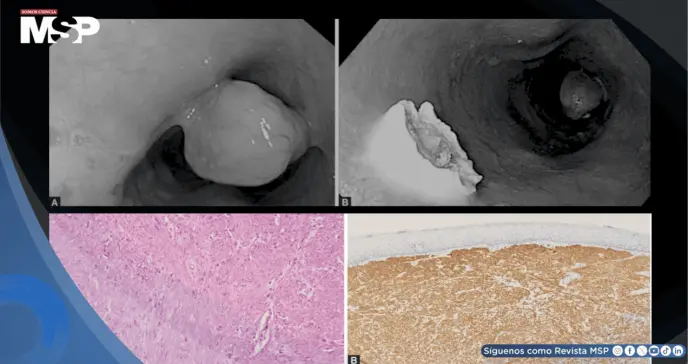

La EDA, realizada con equipo Olympus serie 190, reveló a 20 cm de los incisivos un pólipo pediculado de grandes dimensiones, cubierto por mucosa de aspecto normal y de aproximadamente 3 × 1.7 × 1.5 cm.

La superficie de la cabeza y el pedículo del pólipo no mostraban irregularidades, y ambas zonas teñían de forma homogénea con solución de Lugol. Al tacto con pinzas, el pedículo se mostró blando y flexible. El pólipo fue resecado completamente mediante polipectomía con asa diatérmica.